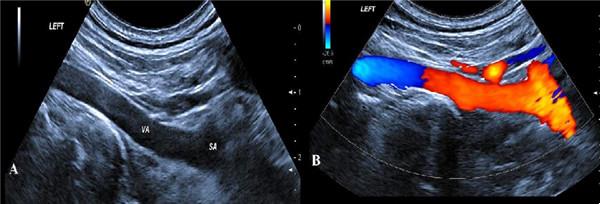

二、開(kāi)的是“彩超”,為什么是黑白的?

彩超的“彩”指彩色多普勒,并非指屏幕是彩色的,所有的超聲都是基于二維超聲,“彩色”是反映的血流情況,咱們醫(yī)院的四維彩超儀器可都是國(guó)際一流設(shè)備GE及Philips品牌。